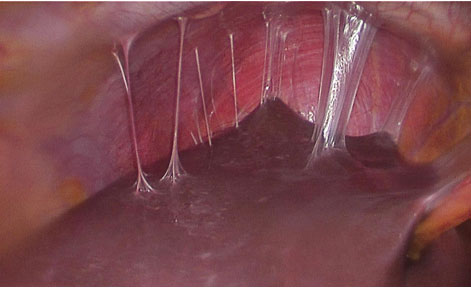

HYALOGLIDE ACP® (kendiliğinden çapraz bağlı polisakkarit) bazlı, steril, şeffaf ve yüksek derecede viskoz bir jeldir. İnsan bağ dokusunun, epitel ve mezotel dokuların ana kompenentlerinden biri olan hiyaluronik asidin kondensasyonu ile elde edilir. Yapışkanlığı sayesinde, HYALOGLIDE, doku yüzeyinde mükemmel bir şekilde yapışır. Böylece cerrahi işlemin ardından tamir aşaması boyunca komşu dokuları ayrı tutan ve zaman içinde tamamen emilen bir yapışma önleyici bariyer yaratır.

• Geçici mekanik bariyerin doku yüzeyine yapışması için yüksek viskozite. Yaklaşık 10 günlük dayanma süresi sayesinde etkili bir bariyer görevi görmektedir. Kendiliğinden biyo parçalanma ile tek yan ürün olarak sadece saf hiyaluronan açığa çıkarmaktadır.